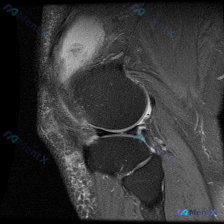

刚刚整理了一份很有启发的膝关节MRI读片病例,分享给大家,这个病例最有意思的点就是预设问题和实际影像发现不一致,很考验读片思路。 病例基础信息 这是一张膝关节矢状位T2加权MRI图像,需要评估是否存在半月板异常,图像质量清晰,能看到股骨远端、胫骨近端、髌骨、髌下脂肪垫、关节间隙等全部关键结构。 影像...

看到这张膝关节MRI矢状位T2序列的影像,整理一下分析思路,和大家一起讨论。 先整理影像核心发现 这是单张膝关节MRI矢状位T2序列影像,核心异常如下: 1. 骨骼结构:股骨远端、胫骨近端、髌骨轮廓完整,无明显骨皮质断裂 2. 韧带:前交叉韧带(ACL)走行可见,但近股骨附着点和中段低信号连续性不佳...